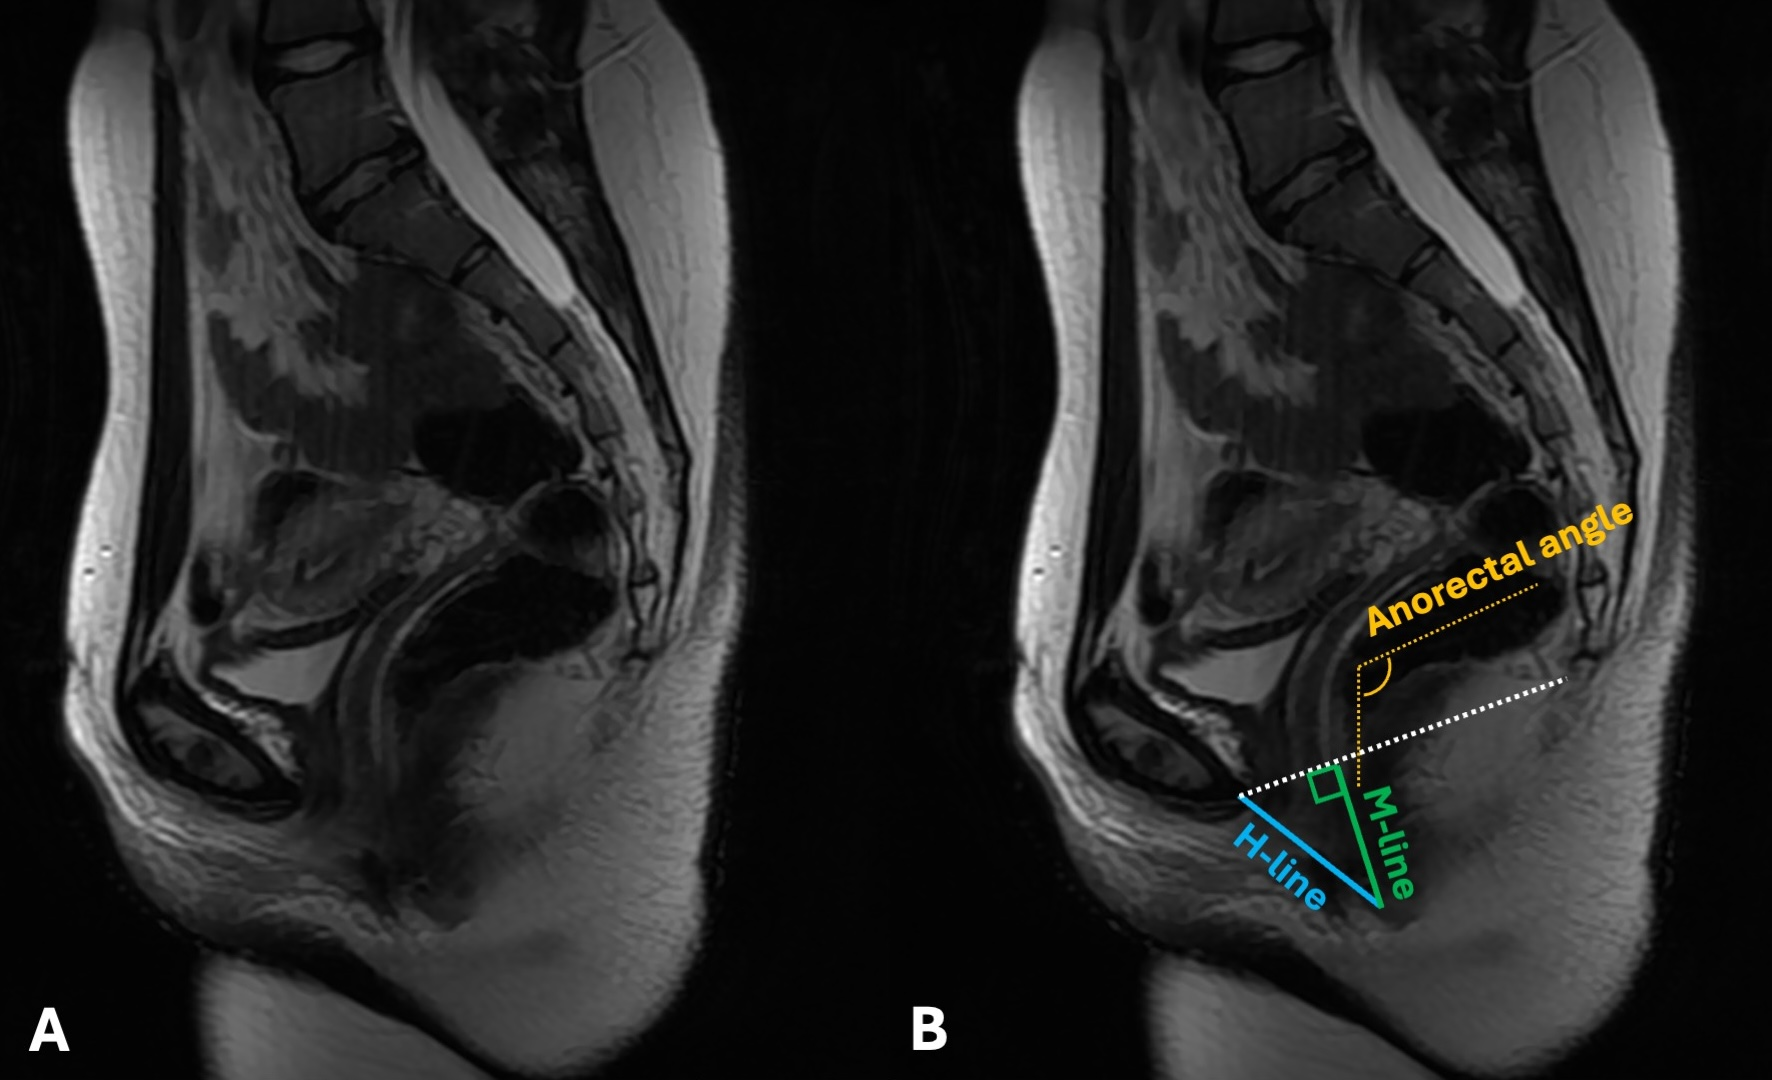

At each patient’s latest follow-up, the most recent CT scans were used on sagittal view to calculate the Hiatal line, the Muscular line, and the anorectal angle. The Hiatal line (H-line; drawn from the inferior margin of the pubic symphysis to the posterior aspect of the anorectal junction and representing the diameter of the levator hiatus) measures the width of the levator hiatus. A standard H line measured at rest is typically less than 6 cm. Eventual widening can weaken the pelvic floor’s ability to support organs and increase the chance of pelvic floor prolapse. The Muscular line (M-line; extends perpendicularly from the pubococcygeal line to the posterior aspect of the H line and represents the vertical descent of the levator hiatus) indicates the relaxation or descent of the levator hiatus, therefore directly portraying pelvic floor prolapse. In healthy patients, the M-line measures less than 2 cm. An M-line longer than 2 cm is suggestive of pelvic floor descent. The two lines are often used in conjunction to assess the overall anatomical health and function of the pelvic floor.

The anorectal angle is the angle drawn between the central axis of the rectum and the central axis of the rectum. The normal values range from 70 to 134 degrees. It is considered a factor in fecal continence and defecation, influenced by the puborectalis muscle.

In cases where monolateral pubic resections were performed (involving the pubis symphysis), the contralateral side was used as a landmark for the anterior end of the H-line (Figure 3).

Figure 3. On the left, a sagittal MRI scan of a pelvis as it appears without notes (A). On the right, the same image with illustrations of patient’s anorectal angle (yellow), H-line (blue), and M-line (green) (B).